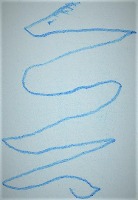

Parkinson's Disease Early Detection: This model can be used in telemedicine and eHealth applications to analyze drawings or handwriting samples drawn by patients. Early diagnosis of Parkinson's Disease can help in beginning the treatment early and slow down the progression of the disease.

Medical Research: Researchers studying Parkinson’s Disease can use this model to analyze large sets of drawings or handwritings, identifying trends and correlations between identified Parkinson’s Disease positive cases and the characteristics of their drawing.

Home Monitoring System: This model can be incorporated into a home monitoring system where elderly individuals or at-risk populations can regularly submit handwriting or drawing samples. These can be analyzed for Parkinson's symptoms, enabling early intervention and care.

Rehabilitation: For those patients already diagnosed with Parkinson's Disease, this model can help monitor the progression of their disease based on regular analysis of their handwriting or drawings. This would facilitate tailoring their treatment and rehabilitation program based on their current status.

Pharmaceutical Industry: Drug companies can use this model in clinical trials to monitor the impact of new Parkinson's Disease drugs on patients. This can provide valuable data on the effectiveness of the drugs, based on whether they help improve the drawing and handwriting symptoms associated with Parkinson's.